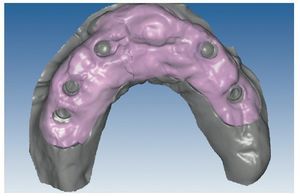

Mediante el uso de un escáner óptico de luz estructurada, los protocolos CAD registran los primeros datos relativos al modelo maestro con las correspondientes posiciones de implante (figs. 87 y 92). En el siguiente paso tiene lugar la digitalización de la planificación, previamente realizada en cera de escaneo matificada, de la restauración definitiva (figs. 88, 90 y 93). La subsiguiente conciliación de los datos mediante el uso del software de diseño dental permite al protésico planificar virtualmente el resto del procedimiento (figs. 89 y 91, 94 a 96) a partir del diseño de las estructuras (figs. 97 y 98).

Fig. 87. Imagen CAD del modelo maestro superior.

Fig. 92. Imagen CAD del modelo maestro del maxilar inferior.

Figs. 94 a 95. Planificación CAD de la estructura del maxilar inferior, en representación lingual y vestibular.

Figs. 96 a 98. El diseño definitivo de la estructura del maxilar inferior, desde distintas perspectivas.